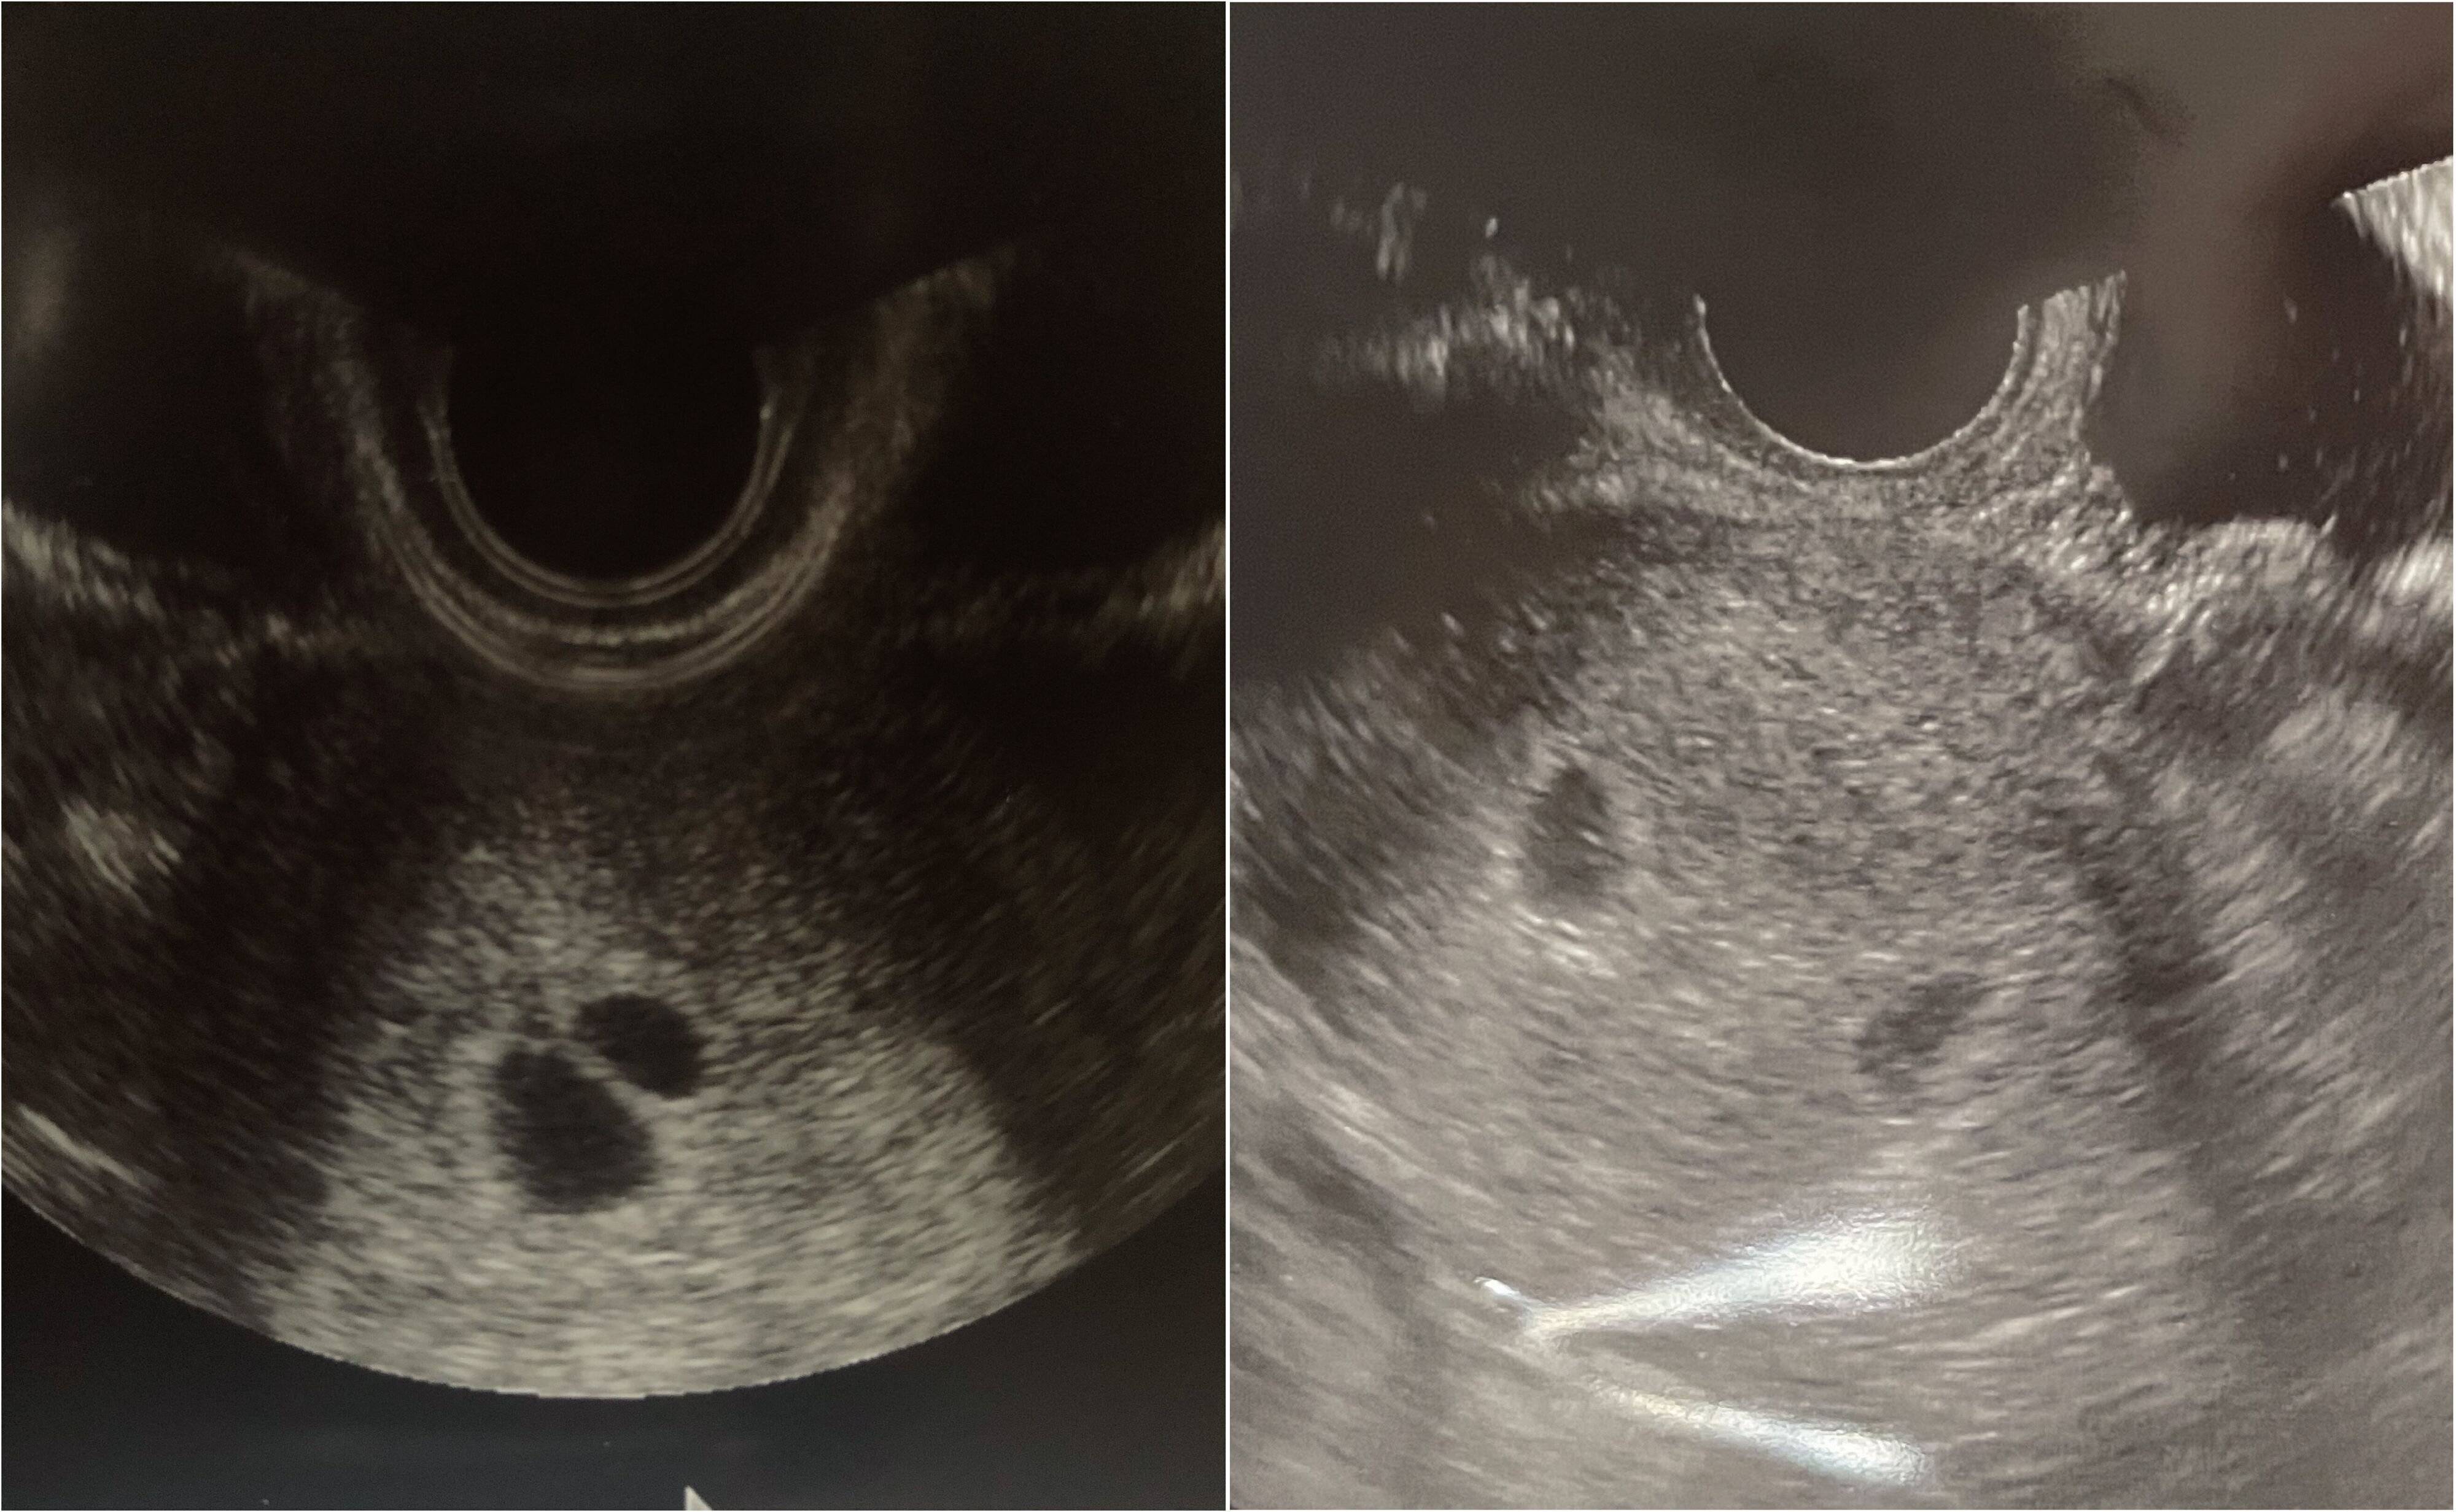

2回の妊娠がわかったときのエコー写真。左がいとちゃん&うたちゃんのときのもの、右がももちゃん&はるたくんのとき。 -